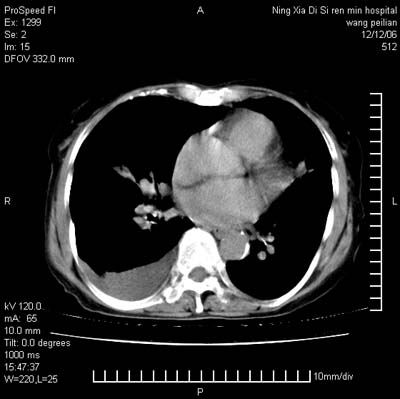

标题: CT5609:胸部:女77 病史不详 [打印本页]

标题: CT5609:胸部:女77 病史不详

两肺可见多个大小不等的结节,左侧有胸水,纵隔淋巴结增大,考虑是细支气管肺泡癌

两肺尖纤维索状影,两下肺结节块状影,且有钙化灶,右胸腔积液。考虑肺结核并胸膜炎。

两肺尖纤维索状影,两下肺结节块状影,且有钙化灶,右胸腔积液。考虑肺结核并胸膜炎肺间质纤维化

考虑:1、慢性支气管炎合并全小叶型肺气肿、间质纤维化;

2、双肺结核;

3、右侧胸膜炎(积液)。

1、双肺继发型肺结核(以纤维、增殖灶为主);

2、右侧胸腔积液;

3、其余符合老年肺改变。

双肺见多个结节状及条索状影,双侧胸腔积液,右侧叶间积液,考虑结核性胸膜炎